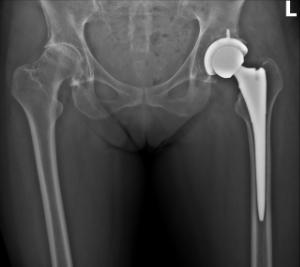

Left Hip 1

February 3, 2019